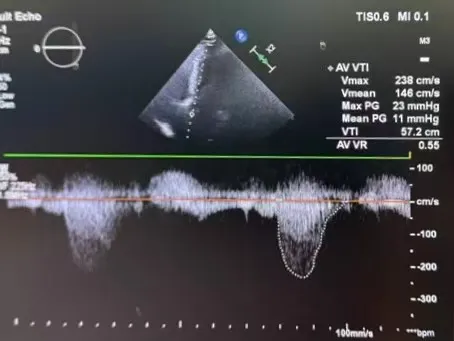

周达新教授 复旦大学附属中山医院 共识引路,干瓣启新,共赴临床解决方案:当前,结构性心脏病的介入治疗已迈入微创化、精准化的新时代。技术的革新、创新器械的上市,都是我们中国技术领跑的印证,《专家共识》的应运而生是中国医生对于行业“规范化”的践行,让治疗更精准、让医者更贴近“以患者为中心”的医疗本质。 潘文志教授 复旦大学附属中山医院 严谨求真重思考 创新临床互验证:在医学的漫长征途中,新器械的突破与严谨的临床研究是两大核心驱动力。拥抱创新的同时需要严谨求证,预装干瓣作为创新器械,其即取即用的特性可以很好的适配“急诊”的场景,此外,国产创新不是简单的复制,干瓣的瓣叶质地不是字面意思“干”的,而具“曲柔性”。所以,需要多看多测,才能全面了解一款产品。《经导管心脏瓣膜治疗术》的问世也是凝结着我们带着临床思维思考的结晶的“独家秘笈”,希望能够将“来时的路”变成未来行业同行者的“高效学习之路”! 患者病史 多病共存陷困境,主动脉瓣狭窄成 “首要威胁” 现病史:患者反复活动后胸闷2年余,无胸痛、心悸,无头晕、晕厥等不适,未予重视。患者轻微体力活动(快走、爬楼梯)即胸闷气促,静息及夜间无不适,无咳嗽、心悸等症状。为进一步诊疗收入我科,患病以来精神、食欲、睡眠、二便及体重均正常。 既往史: 2025年5月7日因小便不畅至外院住院病理穿刺确诊前列腺癌,期间检查心超提示主动脉瓣钙化伴重度狭窄,遂暂缓前列腺手术。2025年05月30日至我院就诊。 2025年5月20日开始服用比卡鲁胺片。患者血脂异常,长期服用丹参滴丸,麝香保心丸,心通颗拉。 手术史外伤史:10年前行肺手术,具体不详。否认外伤史。 入院检查 心电图提示:窦性心动过缓;ST-T改变; 心超显示:主动脉瓣钙化伴重度狭窄及轻度反流,Vmax 4.8m/s、PGmax 93mmHg、PGmean 47mmHg;左房增大,左室壁增厚。 冠状动脉CT造影:左前降支中段浅表心肌桥,主动脉瓣增厚伴重度钙化,主动脉粥样硬化。 术前CT 三叶瓣,中度钙化,主动脉根部直径25.4mm,LVOT直径23.5mm 双侧冠脉开口高度尚可,瓦氏窦尚可,ST尚可,升主尚可,冠脉风险小;中度钙化,心脏角度39.2°;心腔内径可,左室壁增厚。 外周走行尚可,全主动脉存在散在钙化,右侧穿刺点需避开钙化,血管内径可,血管内壁存在纤维增厚。 手术策略:右侧股动脉为主入路,使用20F大鞘;20球囊预扩,植入AV29瓣膜; 手术过程 主动脉根部造影 输送系统柔顺过弓 定位 缓慢释放瓣膜 造影观察 稳定脱钩 最终造影性钙位置良好,轻微瓣周漏 术后超声:轻度瓣周漏,术后平均压差11mmHg 出院前超声:平均压差11mmHg 在多基础疾病患者日益增多的当下,该病例也为临床提供重要启示:针对合并肿瘤、既往手术史的复杂瓣膜病患者,需通过多学科协作(心内科、肿瘤科、麻醉科等)全面评估病情,结合精准影像技术与适配器械,制定个体化手术方案,才能在保障安全的同时,实现最优疗效。 作为中国结构性心脏病领域的标杆学术活动,中国结构周 2025为这类高水平临床病例提供了交流平台,助力推动我国结构性心脏病诊疗技术持续创新,让更多复杂瓣膜病患者受益于精准医疗方案。 ProStyle A®预装干瓣——助力临床最优化解决方案: 轻松过弓,精准可控:该病例全主动脉存在散在钙化,右侧穿刺点需避开钙化,ProStyle A®较细的尺寸+柔顺的输送系统通过性能得到了很好的验证; 平稳释放:平衡的径向支撑力降低了释放过程中的张力,流入端小锥角设计能够迅速锚定贴边; 预装干瓣 便捷顺安:金仕生物专利抗钙化技术运用纳米技术去除组织内的细胞碎片和磷脂,封闭游离醛基,从根本上阻断了瓣膜钙化的多项因素,显著提升了瓣膜的耐久性;同时,相比较传统戊二醛保存方式,干式存储最大限度的保留心包的亲水亲油平衡,还原组织天然曲柔性,进一步保障了瓣叶开合,保证长期耐久性; 专家简介 葛均波 复旦大学附属中山医院(点击查看专家详细简历) 周达新 复旦大学附属中山医院(点击查看专家详细简历) 潘文志 复旦大学附属中山医院(点击查看专家详细简历) · END ·